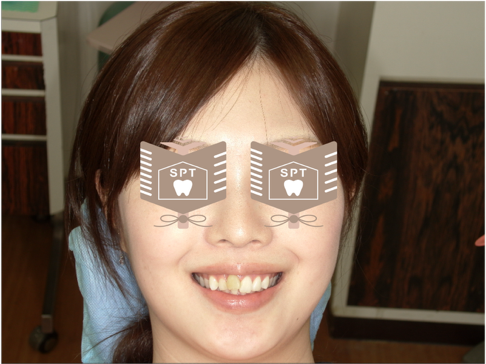

25歳、女性の方で、右の前歯が飛び出でるように見えるのを何とかしたいのと、他院でホワイトニング治療したが、飛び出ている歯だけ白くならなかったので白くして欲しいとのことでした。

口腔内を診察させていただきますと、右上1(右上の1番前の歯のこと)が唇側転位していました。それと他の歯に比べてやや暗い歯の色調でした。

治療前のシミュレーション

まず完成した時の歯の感じを患者様に確認してもらうために、模型を作成しました。やはり歯の歯茎部のラインがどうしても揃わないので、歯だけを見ると整った感じにはならないのですが、患者様は笑った時にあまり口唇が上がらない方だったので歯茎部はあまり見えませんでした。上記のことや模型を確認して納得していただいた上で治療を進めていきました。